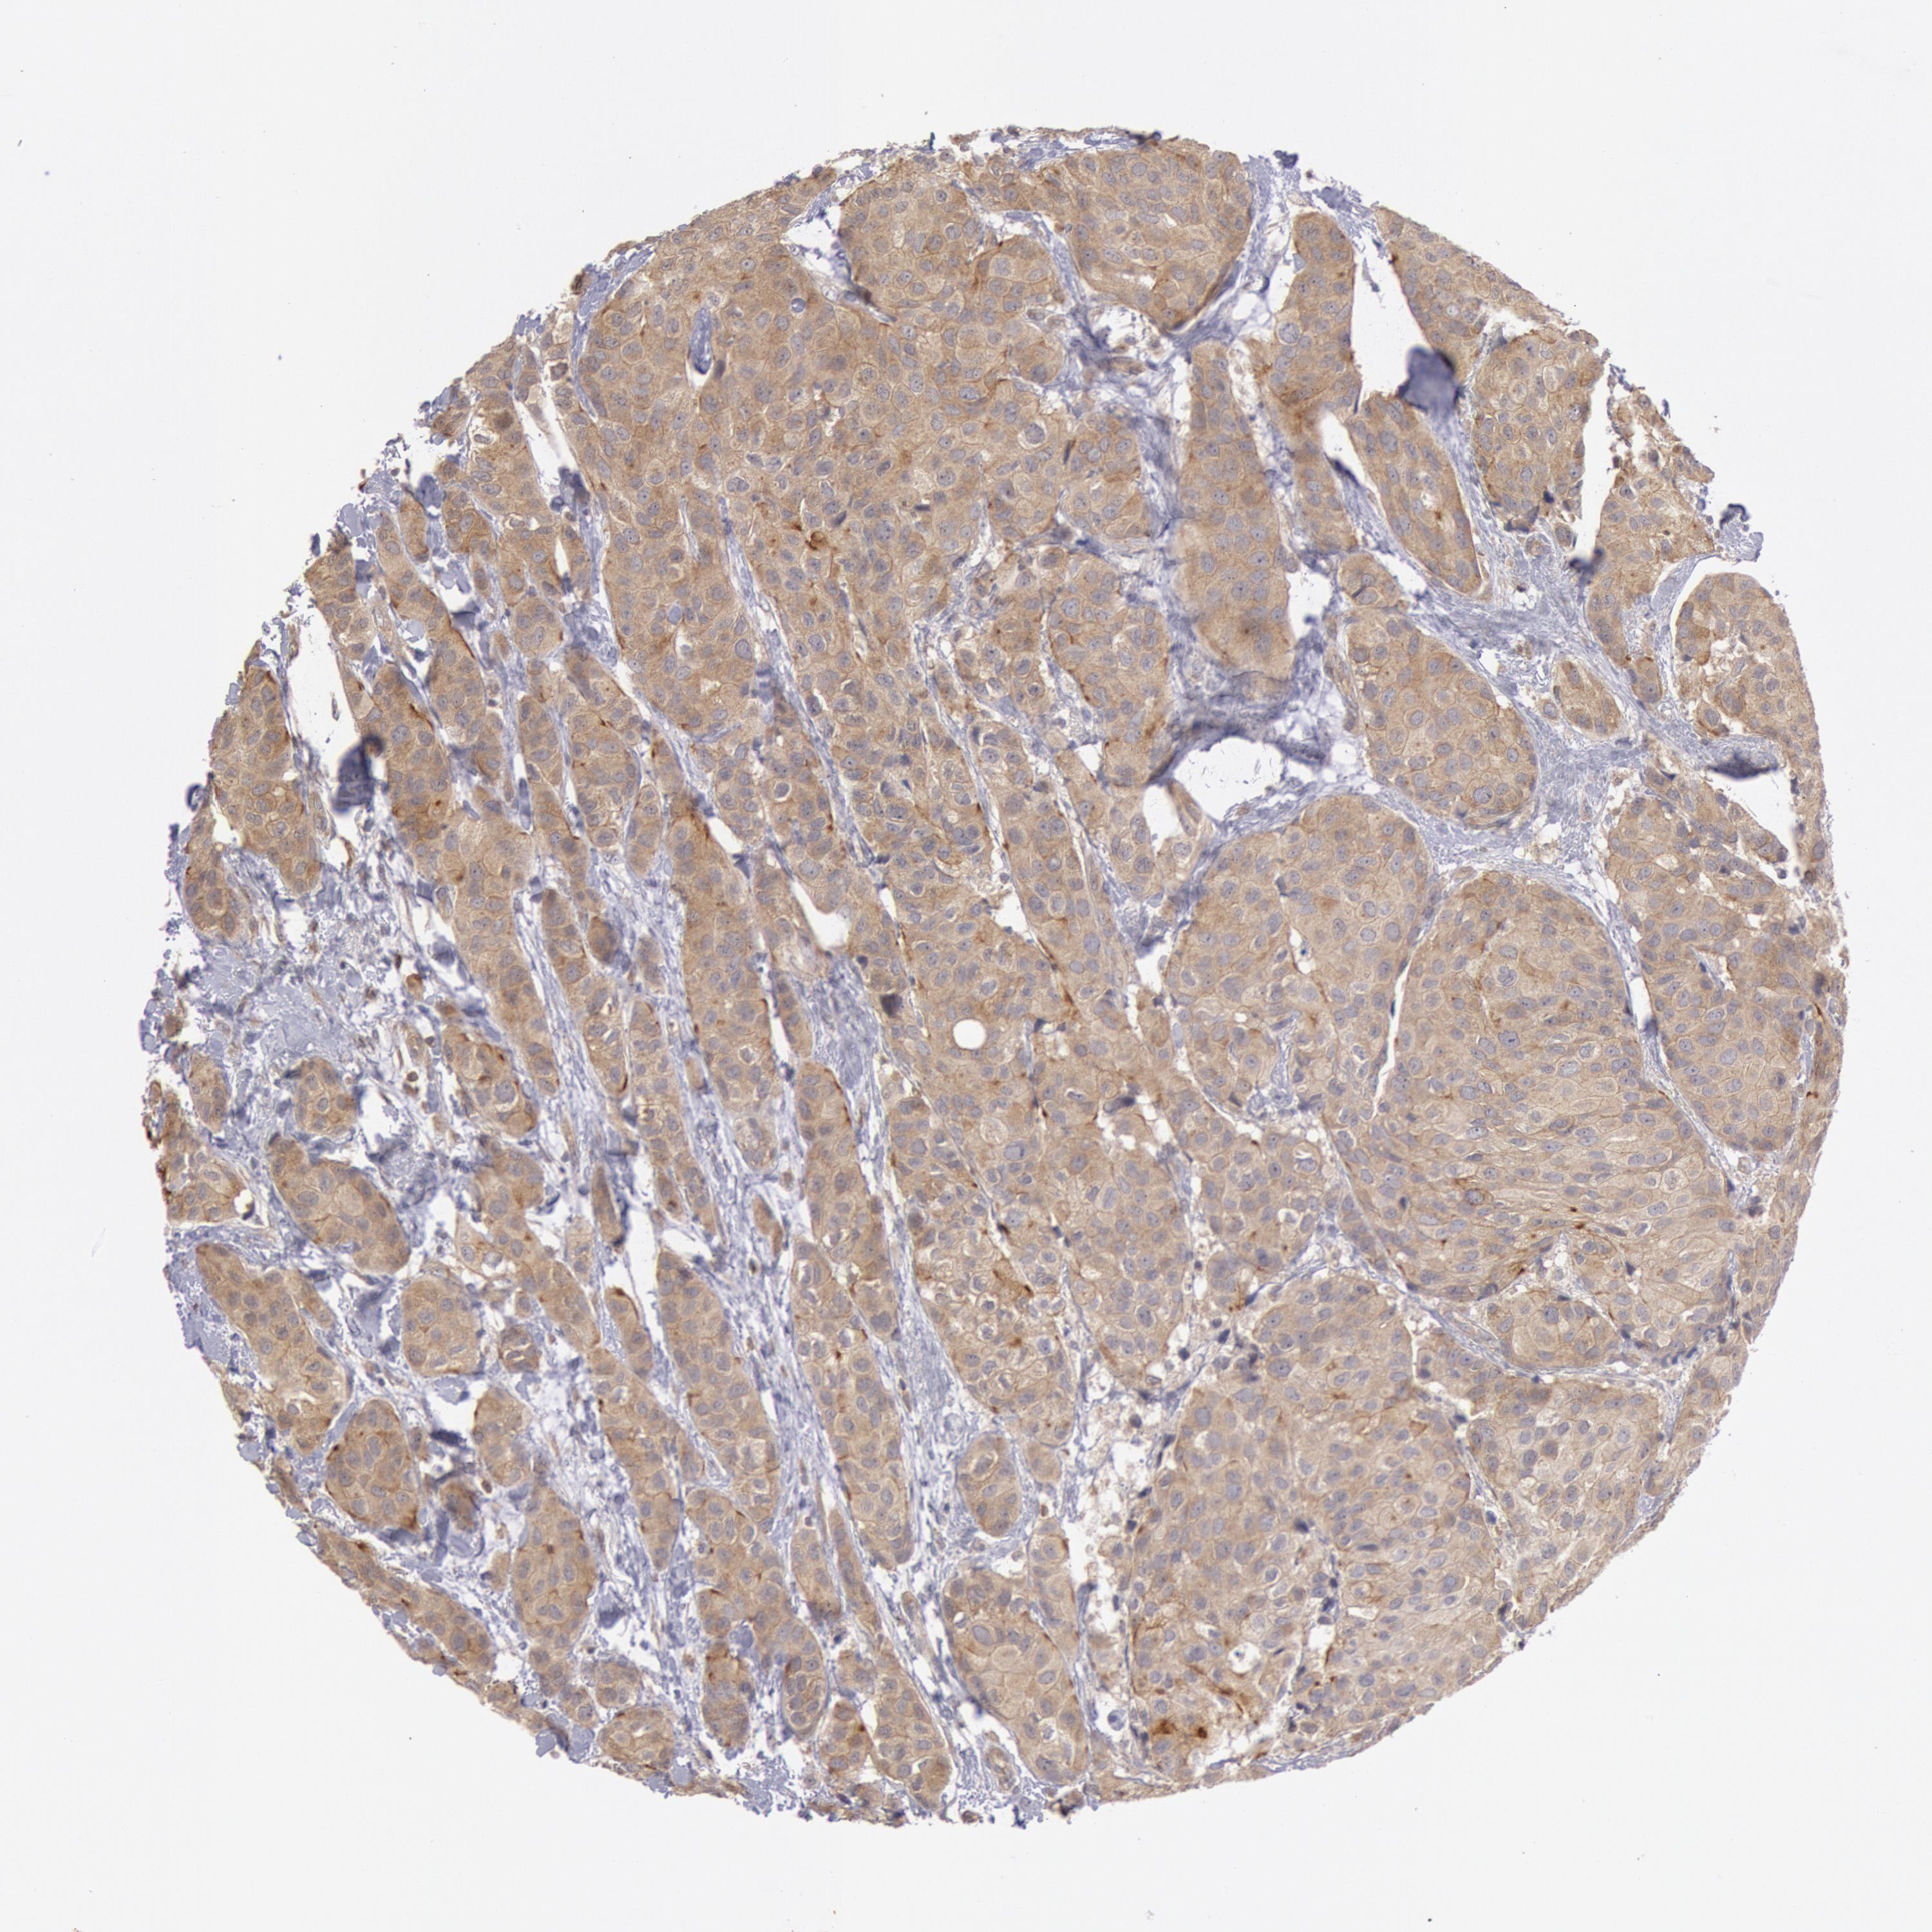

BRCA TCGA BRCA VALIDATION PROTEIN EXPRESSION